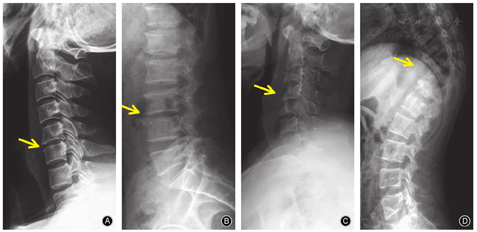

X线检查广泛应用于腰痛患者,但其敏感性很低,特别是在布鲁杆菌性脊柱炎的早期。由于布鲁杆菌性脊柱炎是一种进展缓慢的疾病,仅25%患者在入院时有放射学异常,X线检查通常在发病后2个月或更长时间才可观察到变化[2,9]。多累及腰椎,边缘型骨质破坏最常见,椎体中心亦可被侵犯,死骨少见,无椎体压缩征象,椎间小关节间隙变窄甚至消失,椎间隙狭窄,下腰椎可见自下而上的渐进性前、后纵韧带钙化[10]。骨质破坏较脊柱结核轻,病变周围出现骨赘增生,骨赘可沿椎体终板前缘增生,形成典型的"鸟嘴"状(图1A,图2A,图2B),反应性骨改变发生早于脊柱结核(表4)[20]。

脊柱结核早期X线通常显示正常表现,只有出现30%的骨丢失后才可见椎体变化,因此,X线检查对脊柱结核的早期诊断无价值[17,18]。X线片主要表现为椎体骨质破坏,侵犯椎间盘,椎间隙变窄,破坏相邻椎体终板,可出现跳跃性破坏,病变以溶骨性破坏为主,骨质增生不明显,后期椎体可出现压缩,脊柱后凸畸形,椎体呈不同程度的变形、变扁、塌陷,不规则骨质破坏,其内可见大小、数量不等"死骨",呈沙粒状居多[12,18](图1B,图2C,图2D,表4)。

布鲁杆菌性脊柱炎在MRI的异常表现主要有[2,16,22,26]:当椎体的虫蚀样骨破坏明显时,T2WI呈不均匀较高信号;而在抑脂像,椎体、椎间盘、附件及椎管内呈不均匀高信号。可以发现椎管内脓肿、炎性肉芽组织突入椎管,抑或是破坏的椎间盘突入椎管。后纵韧带钙化导致相应平面脊髓受压。脓肿为椎旁条状或梭形异常信号影,位于椎前、两侧或椎体后方,脓肿壁呈薄而不规则的增强,且界限不清,无流注脓肿(图1A,图4A,表6)。本团队研究显示布鲁杆菌性脊柱炎较脊柱柱结核病灶内水分子弥散受限程度要高,ADC值的平均值较脊柱结核为低。

脊柱结核MRI显示界限清楚的椎旁异常信号,椎体骨质破坏,T1WI正常高信号的骨髓组织呈信号减低,被病变的低信号代替;T2WI由于病变椎体含水量增加,信号增强,椎体终板常受累,终板破坏致中断甚至消失,为脊柱结核的典型表现[17]。脊椎结核MRI最典型的特点是"跳跃病灶"和薄而光滑的强化脓肿壁(图1B,图4B),以及界限清楚的椎旁异常信号,椎体周围冷脓肿是诊断的重要依据(表6)[12,27]。